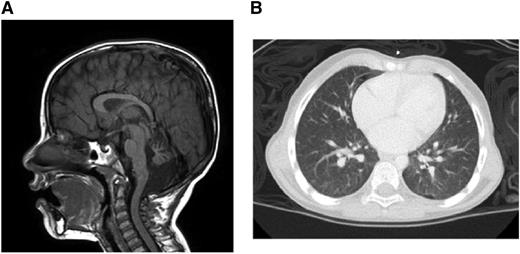

Brain magnetic resonance imaging demonstrated multiple findings including profound atrophy of the cerebellar vermis (Figure 1A). A chest computed tomography revealed diffuse, ill-defined ground-glass nodules and bilateral pleural blebs (Figure 1B). Liver function test results were within normal limits.

Clinical manifestations. (A) Brain magnetic resonance imaging. (B) Chest computed tomography.